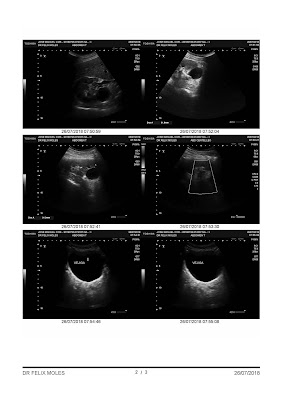

Llamada del de digestivo: En la biopsia había salido que tenía el estomago invadido por un hongo. Me receta medicinas para un mes (Pagándomelas yo, naturalmente) y ya noto una gran mejoría, pero fue a través de un intermediario y o yo lo hice mal o ha sido poco tempo el que me he medicado. Vuelven los dolores.